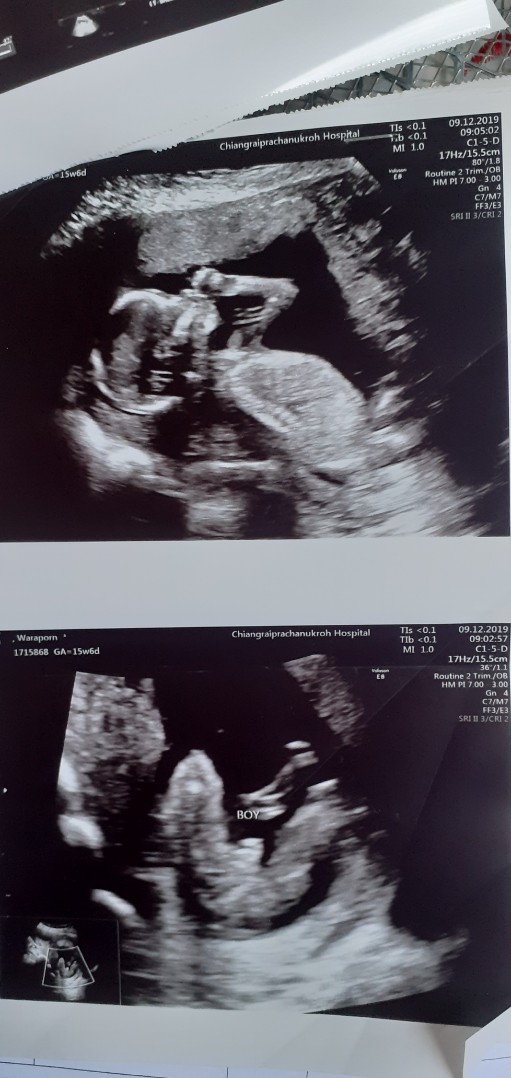

ขอดูใบซาวเด็ก ผช. ของแม่ๆ หน่อยค่ะ ?

ในภาพเป็น ผช ใช่ไหมค่ะ พอดีหมอขอชัวร์ๆ เดือนหน้า เลยสอบถามแม่ๆ ที่มีประสบการณ์ลูกชาย หน่อยค่ะ ?ขอดูใบอัตตลาซาวเด็ก ผช . หน่อยจร้าาา? ถาพไม่ชัดเพราะถ่าย VDO มาจร้า ??

ผช คะ

BOY